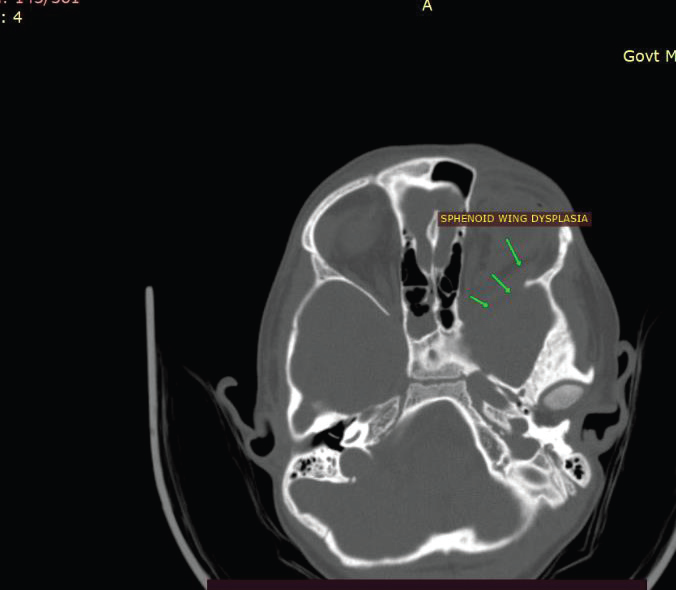

Figure 4: CT brain (axial bone window) of a 39-year-old man suspected to

have NF-1 demonstrates dysplasia of the left sphenoid wing (arrow) with

anterior extension of intracranial contents toward the posterior aspect of the

left orbit.